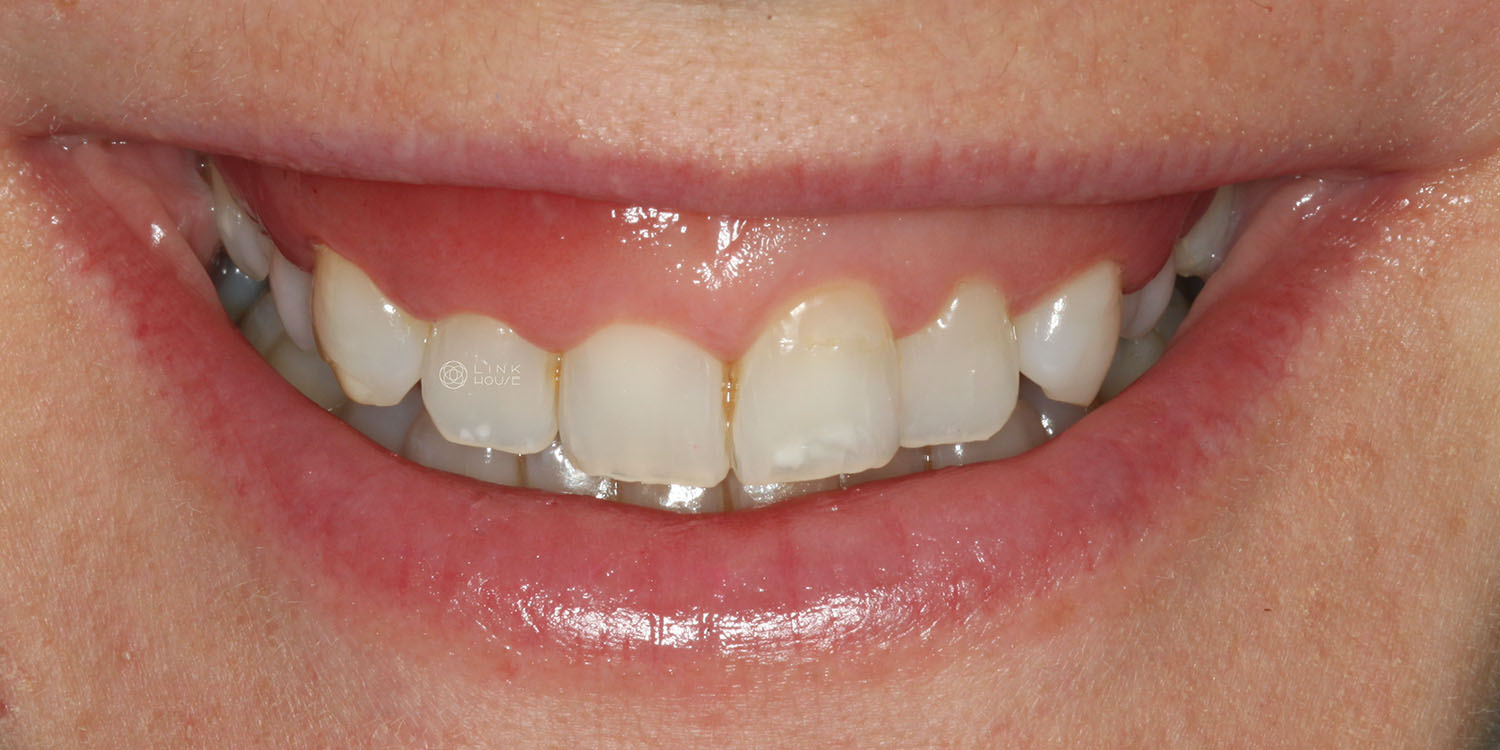

Gummy Smile and Smile Lift

Some people have excess gum tissue that covers part of their teeth. This can make the smile appear “gummy”, where the teeth appear short, and too much gum is visible when smiling.

A gummy smile can also be caused by having worn-down teeth, a high lip/smile line, problems with the eruption of the teeth, some medications, and certain genetic conditions.

If you want to improve your smile’s appearance, a smile lift can help. This involves the removal of excess gum tissue, and sometimes a small amount of bone, to reveal more of the tooth. This procedure can be done on its own or alongside treatments such as veneers.